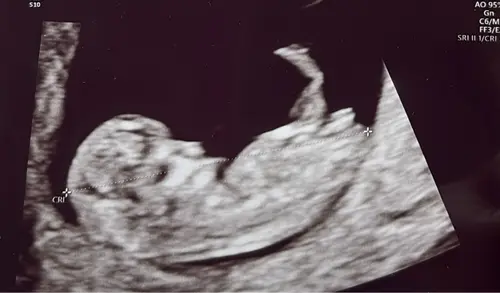

Het is dan met meer zekerheid vast te stellen, maar op basis van de nub-theorie wordt vaak geprobeerd om rond 12–14 weken zwangerschap het geslacht te voorspellen door te kijken naar de hoek van het zogenaamde “nub” (het uitsteeksel waaruit later de geslachtsdelen ontwikkelen):

< 30° t.o.v. de ruggengraat is vaak meisje.

> 30° t.o.v. de ruggengraat is vaak jongen

Ik zie denk ik een jongen

En dat komt doordat het nubje naar mijn idee meer omhoog steekt, maargoed.. dit bied geen officiële garantie 🤭